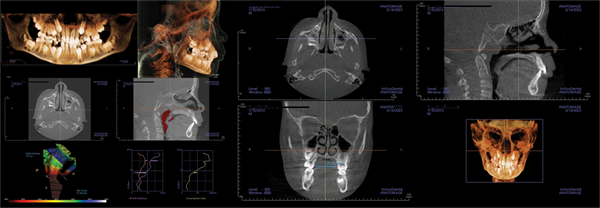

Patient four: Surgical intervention in an adult (Figs. 12–15)

The fourth patient, a 32-year-old woman, presented for an orthodontic examination with a desire to align her teeth. During the examination and discussion, she reported poor sleep and a prior diagnosis of OSA. Her AHI was 77.

CBCT evaluation confirmed these findings. The skeletal examination revealed a slight Class III tendency with a balanced smile.

The panoramic X-ray showed a full complement of teeth with no third molars. The lateral X-ray confirmed the Class III tendency. Her airway MCA measured 74 mm, and her palatal width was 33 mm.

The patient was referred for maxillomandibular advancement (MMA) surgery, with orthodontic preparation. Following surgery, her sleep normalized, with a post-treatment AHI of 1.5 and an MCA of 289 mm. Her facial appearance was relaxed and well-balanced. The patient indicated she would make the same decision again.